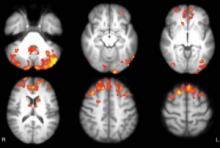

FIBROMYALGIE: Une vraie pathologie, multimodale et multisensorielle